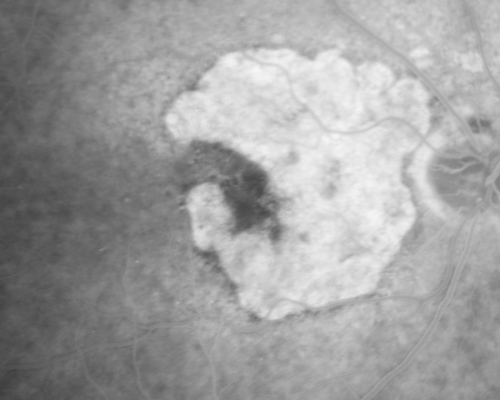

Geographic Atrophy and Age-Related Macular Degeneration - Choriocapillaris is Largely Still Intact

85-year-old woman has age-related macular degeneration in both eyes with geographic atrophy.  She has noticed her vision getting slightly worse in the past 6 months. VISUAL ACUITY:  OD 20/70, OS 20/400